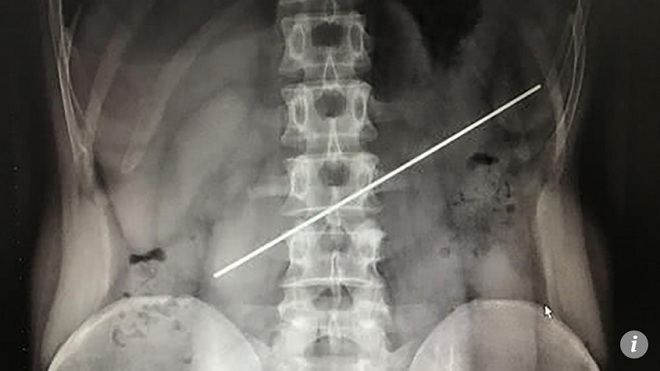

29/04/2018 03:22TQ: Nuốt thanh thép dài 20cm nhận 800 USD, lấy ra tốn gấp 4 lần

Theo tờ Bưu điện Hoa nam Buổi sáng (SCMP), một người đàn ông ở phía tây nam tỉnh Tứ Xuyên, Trung Quốc mới đây đã trải qua ca phẫu thuật gắp thanh thép mỏng đâm thủng dạ dày ra ngoài.

Người đàn ông này thừa nhận đã nuốt thanh thép cách đây hơn một năm trước, trong một màn cá cược khi uống rượu.

Người đàn ông giấu tên đang dần hồi phục sau ca phẫu thuật trị giá 20.000 Nhân dân tệ (tương đương 3.160 USD), truyền thông địa phương đưa tin.

Các bác sĩ cho biết, người đàn ông này nuốt thanh thép dài 20cm, bọc trong vỏ nhựa của một chiếc bút bi, để nhận số tiền 5.000 Nhân dân tệ (792 USD).

Người đàn ông không cảm thấy đau đớn nhưng một năm sau mới, đến bệnh viện để kiểm tra. Ảnh chụp X-quang cho thấy phần cuối thanh thép đâm thủng dạ dày.

Các bác sĩ phẫu thuật trong 1 giờ 30 phút mới gắp được dị vật ra ngoài. Người đàn ông hiện đang hồi phục khá tốt, theo các bác sĩ.